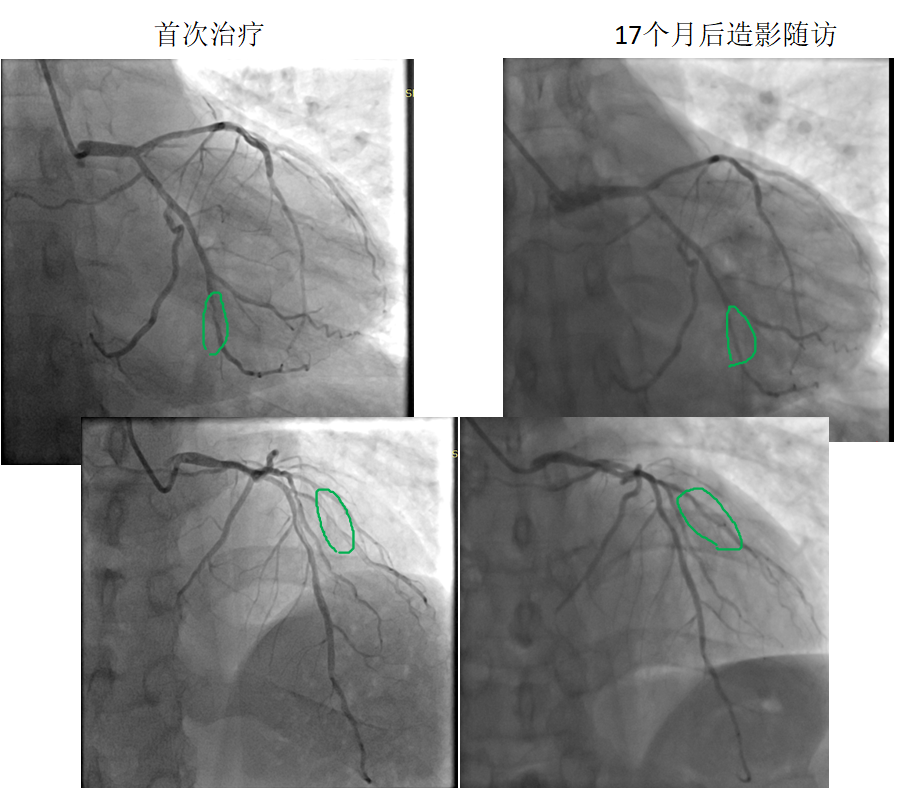

藥物球囊治療原位病變

患者:男,38歲

病變部位: OM中遠段95% ;D1近段90%

使用藥物球囊:2.0 x 20mm; 2.0 x 20mm

17個月后造影

隨訪:OM中遠段20% ;D1近段20%